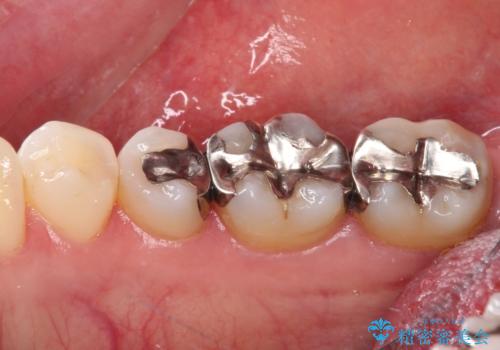

- 銀歯をセラミックにしたいとのことで来院された患者様です。

まず麻酔をして銀歯を外し、むし歯を除去し、形を整えて型取りします。